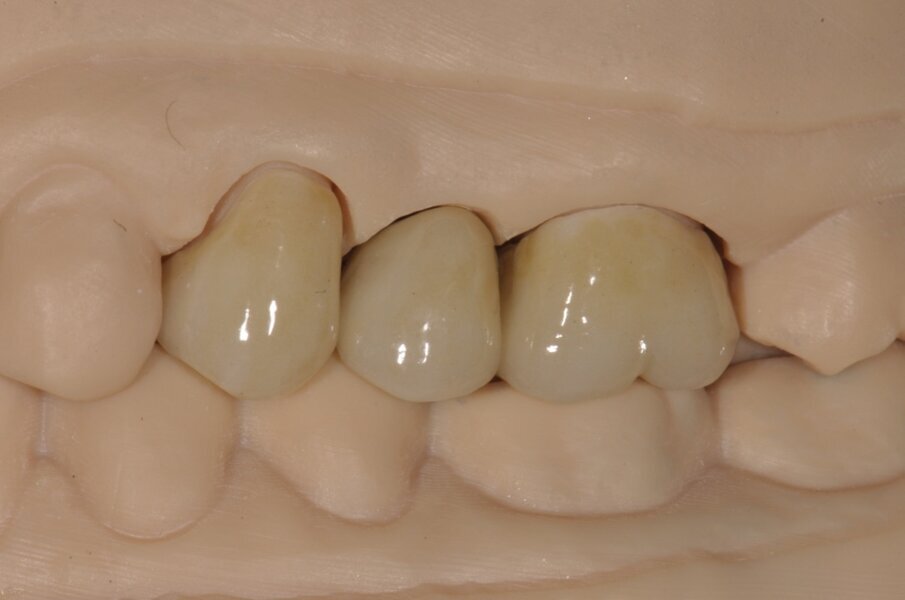

La paziente di 55 anni, non fumatrice, non affetta da alcuna patologia sistemica, da noi trattata con una procedura implantare sostitutiva dell’elemento naturale si era presentata alla nostra osservazione al fine di poter valutare un dolore riferito in sede 2.5 di tipo continuativo tollerabile ma con scarse variazioni di picco algico. L’elemento era stato curato endodonticamente e protesicamente da meno di 1 anno. All’esame obiettivo si presentava una neo protesizzazione individuale su 2.4 e 2.5, mentre su 2.6 si presentava una pregressa protesizzazione in oro-resina con vistosa retrazione gengivale che scopriva un margine corono-protesico impreciso. Il dolore riferito si estendeva tra i 2 premolari in oggetto. Al sondaggio si evidenziava un tragitto patologico di 9 mm in sede mesio-vestibolare della corona in 2.5 (Fig. 1) mentre il sondaggio degli altri elementi si configurava come fisiologico, privo di sanguinamento. L’esame radiografico endorale, mirato al sito ed eseguito con un centratore evidenziava un baffo medicamentale posto mesialmente e associato ad una lacuna ossea adiacente (Fig. 2). La diagnosi di frattura verticale non consentiva alcun recupero radicolare, mentre le radici adiacenti pur avendo delle diafanie periapicali non presentavano sintomi, al fine di un recupero protesico dell’emiarcata si è preferito eseguire una nuova terapia radicolare endodontica (Fig. 3). Fatta la diagnosi si apre un’attenta valutazione sulla tecnica chirurgica, alcune considerazioni vanno fatte sul tipo di estrazione per riuscire ad essere quanto più conservativi, per il mantenimento della cresta ossea vestibolare e per l’architettura gengivale. In tal caso le tecniche atraumatiche prevedono l’utilizzo di strumenti volti alla percussione estrattiva della radice, o al sezionamento obliquo o all’uso di strumenti ultrasonici che lesionano l’attacco dei legamenti parodontali senza intaccare la struttura ossea. Su quest’ultima è ricaduta la nostra tecnica consentendoci di ottenere un sito pulito da frammenti sia ossei che radicolari e riducendo al minimo le lesioni vascolari, senza lembi d’accesso e con un alveolo esangue.

Fig. 1 - Sondaggio parodontale della lesione mesio-vestibolare del dente 2.5.